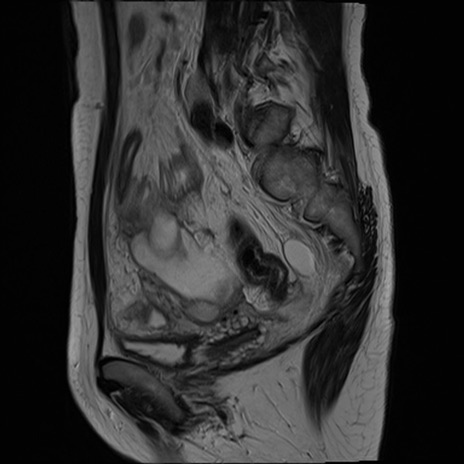

MRI(4日後)

T1WI(横断像)

T2WI(横断像)

脂肪抑制T1WI(横断像)